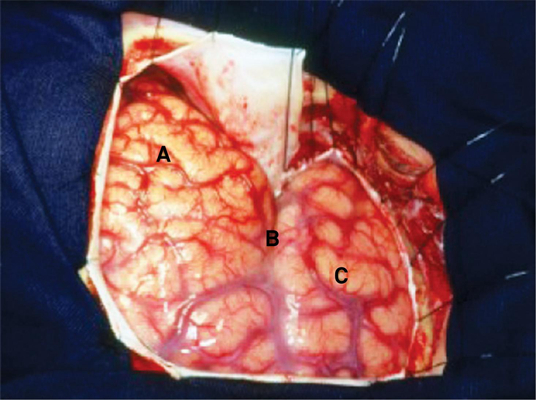

顱內血腫圖片

硬膜下血腫 (5)

硬膜下血腫 (50)

硬膜下血腫 (6)